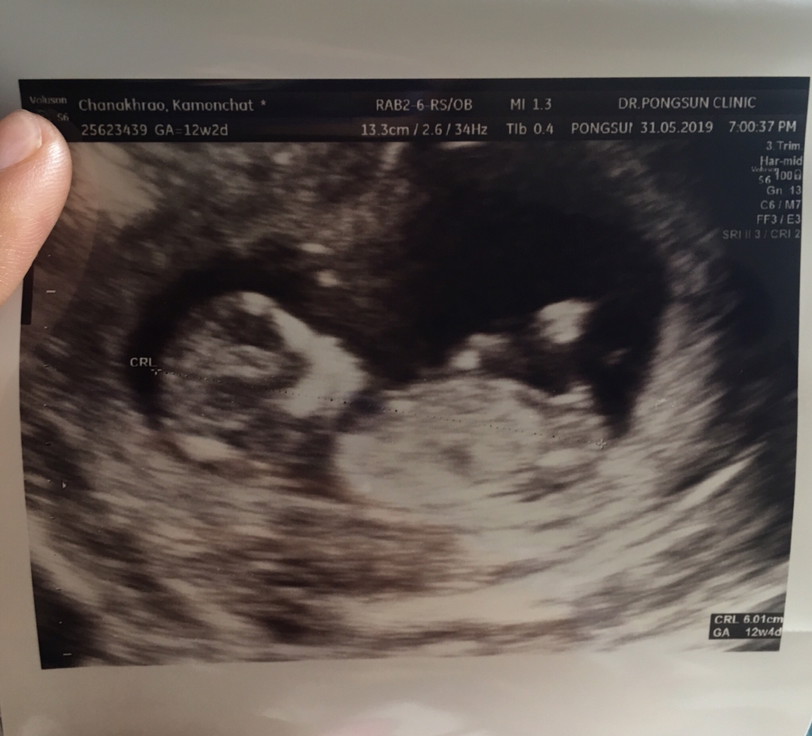

12w2dค่ะ